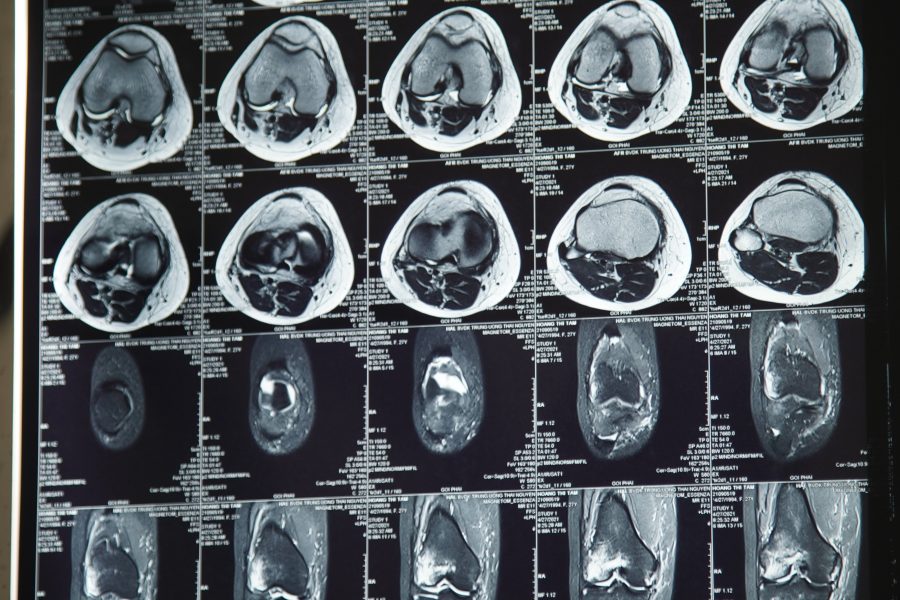

?Chị Hoàng Thị T, 27 tuổi, địa chỉ tại xã Tân Lợi, huyện Đồng Hỷ, tỉnh Thái Nguyên, khoảng 1 tháng trước chị bị ngã sưng đau khớp gối phải, đi lại khó khăn. Chị T tới khám tại Bệnh viện Quốc tế Thái Nguyên, kết quả chụp MRI cho thấy chị bị đứt dây chằng chéo trước khớp gối phải và đứt dây chằng bên mác phải.

Bác sỹ Nguyễn Ngọc Đường- Khoa Ngoại chấn thương, Bệnh viện Quốc tế Thái Nguyên đang theo dõi hình ảnh tổn thương khớp gối trên phim chụp cộng hưởng từ.